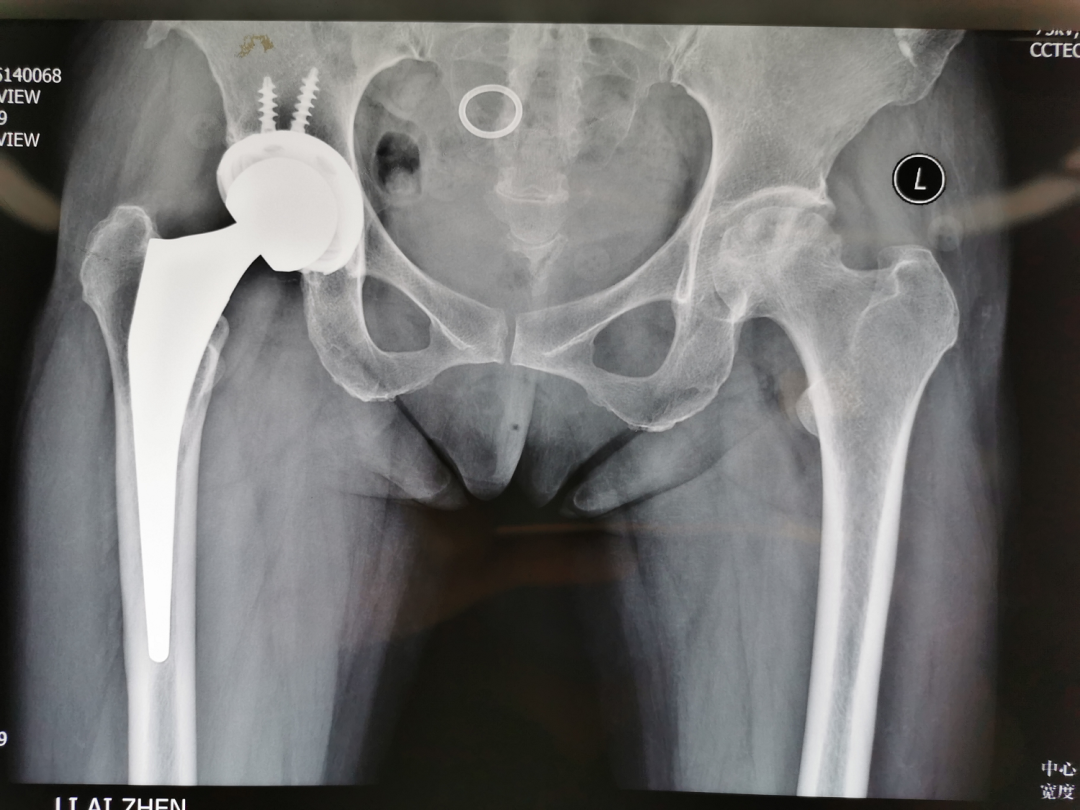

我到洛阳正骨医院学习的第一个科室是髋关节损伤二科,也是洛阳正骨医院髋部损伤中心,以髋关节置换手术最为有名。第一天的第一台手术是髋关节置换手术,由中原地区髋关节置换大咖刘主任主刀,很有幸我能够跟这台手术。刘主任采用的是外侧入路前侧脱位。这也是我从没有见过的手术方式。切开皮肤后,切除部分前侧关节囊后很快暴露了股骨头,视野很清楚。截骨、取头、脱位,先处理股骨侧,再处理髋臼侧,20分钟完成了缝合前的各种步骤,这令人惊讶的手术速度!

3. 手术步骤的衔接紧密,术中没有浪费的动作。在髋部损伤二科,我一共参与了大约60台关节置换,也对关节置换有了一定的体会。